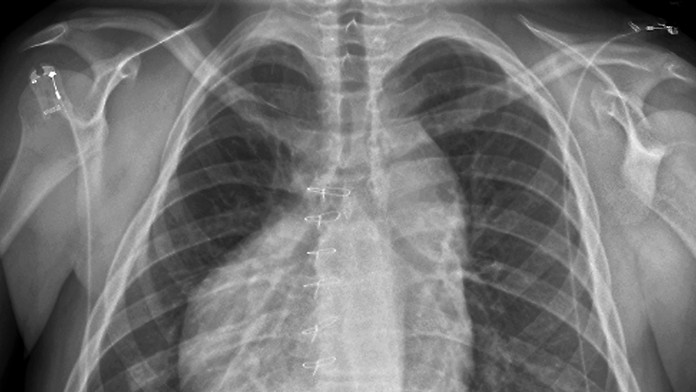

V šoku bol lekár aj sám pacient: Muž mal srdce na nesprávnom mieste

Pri bežnom röntgenovom vyšetrení objavil odborník vzácnu vrodenú vadu.

Pri bežnom vyšetrení röntgenom narazil Diego Diaz, odborník na magnetickú rezonanciu a röntgenové vyšetrenia, na niečo mimoriadne vzácne.

Keď sa pozrel na snímku pacienta, zistil, že sa jeho srdce nachádza na pravej strane hrudníka. V prvej chvíli mu napadlo, že röntgenová snímka je chybná. Srdce na druhej strane hrudníka však majú ľudia so vzácnou vrodenou vadou, ktorá sa nazýva dextrokardia.

„Najprv mi napadlo, že ide o chybu obrazu. Následne, keď som sa druhý raz uistil, som si uvedomil, že je to skutočná poloha srdca,“ povedal pre Newsweek.

Lekár Diego Diaz pracuje v New Yorku a niečo podobné videl prvýkrát. Dextrokardia postihuje približne jedného človeka z 12 000.

Hoci dextrokardia môže byť úplne neškodná a väčšina pacientov s touto vadou žije normálny život, niekedy môže byť spojená s ďalšími zdravotnými problémami.

Ani sám pacient o tejto anomálii vo svojom tele netušil. Išlo o preventívnu zdravotnú prehliadku a preňho samého to bol veľký šok. Lekár aj v tejto súvislosti poukazuje na to, aké dôležité sú návštevy u lekára, a to aj v prípade, že sa cítite zdravo.